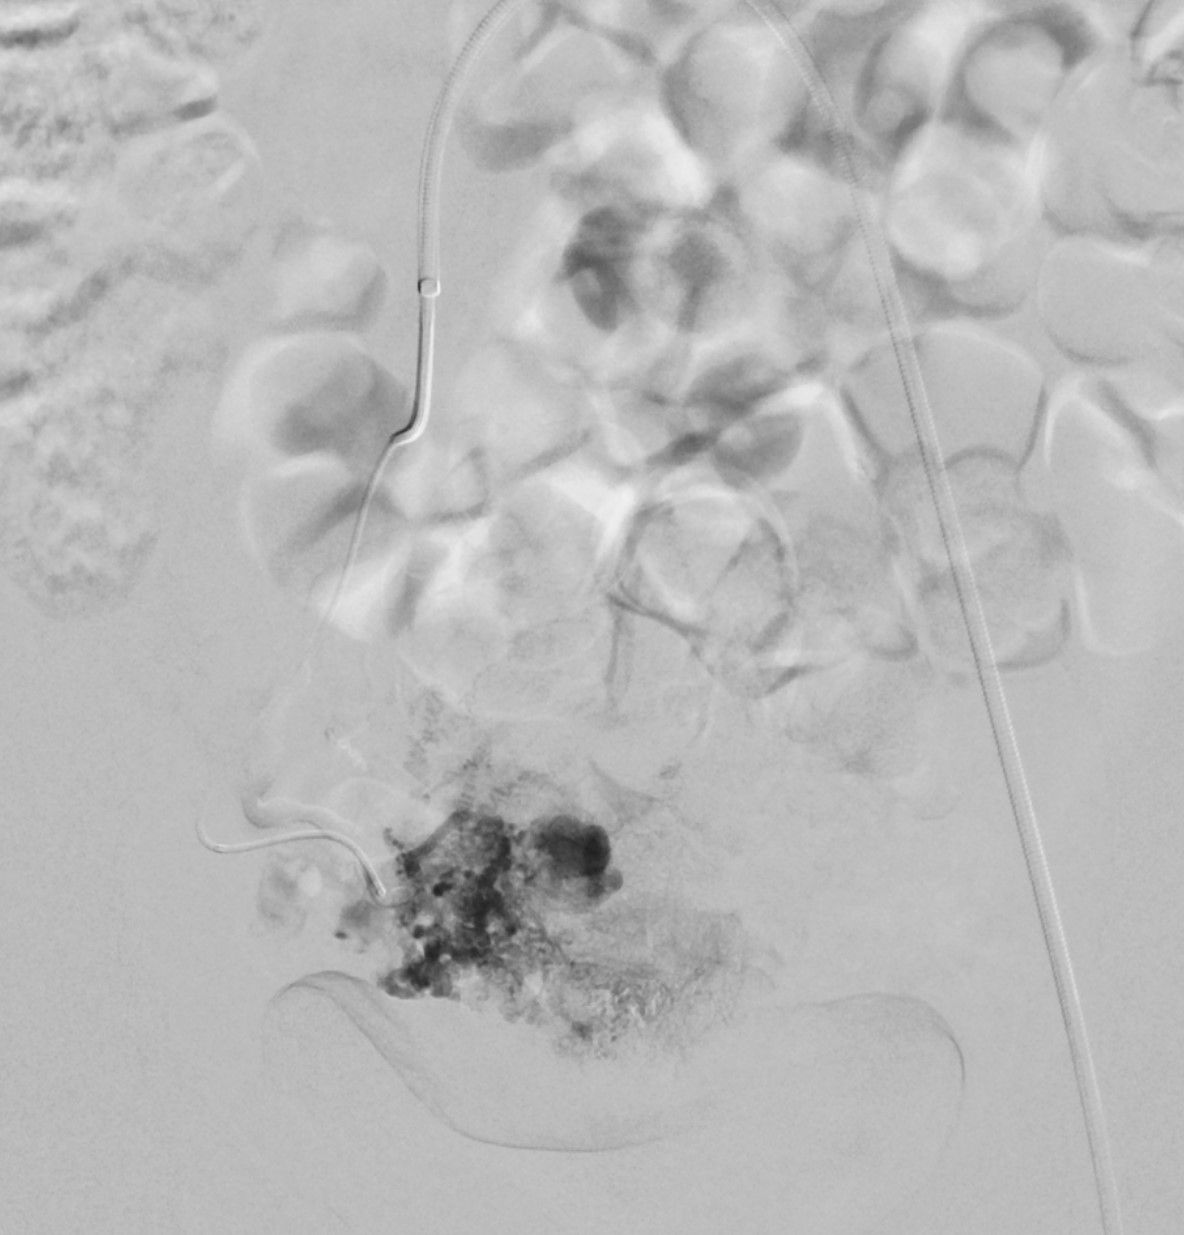

A 35-year-old female is two weeks postpartum after a caesarean section delivery. She presented to the emergency room with sudden brisk vaginal bleeding. What is the most likely diagnosis?